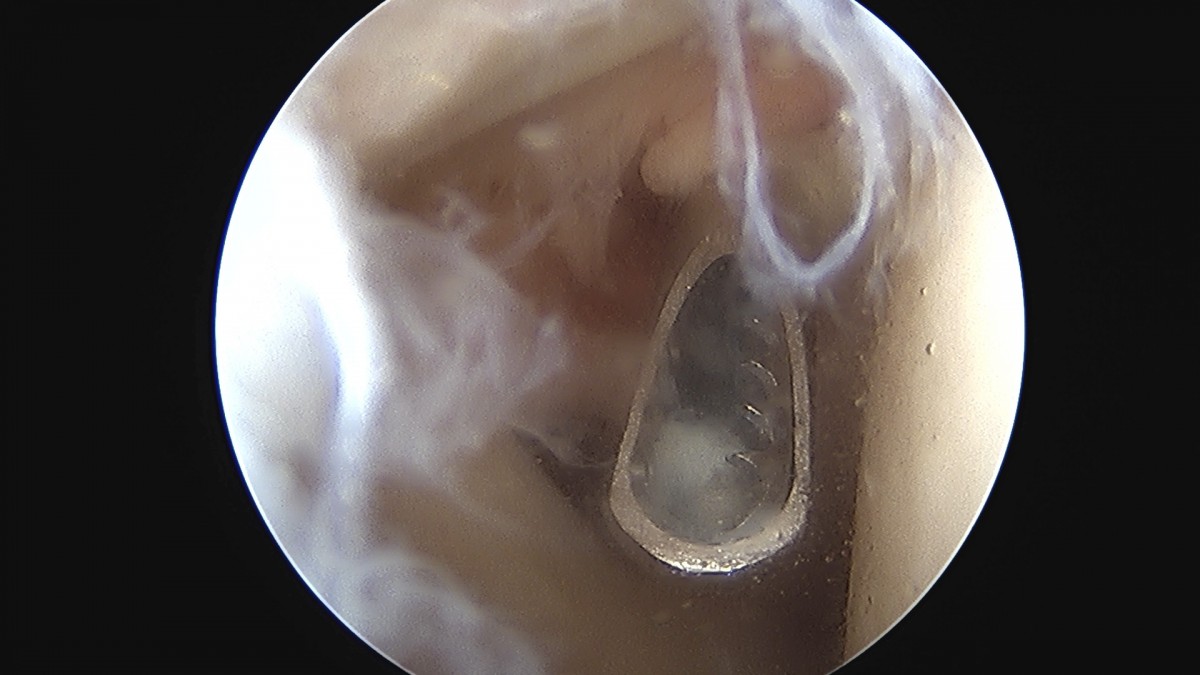

정지영원장님 어깨 회전근개 봉합술 임채O 환자

dae765e4d9ac96aee867c9d6292d8784_1758009113_1082.jpg